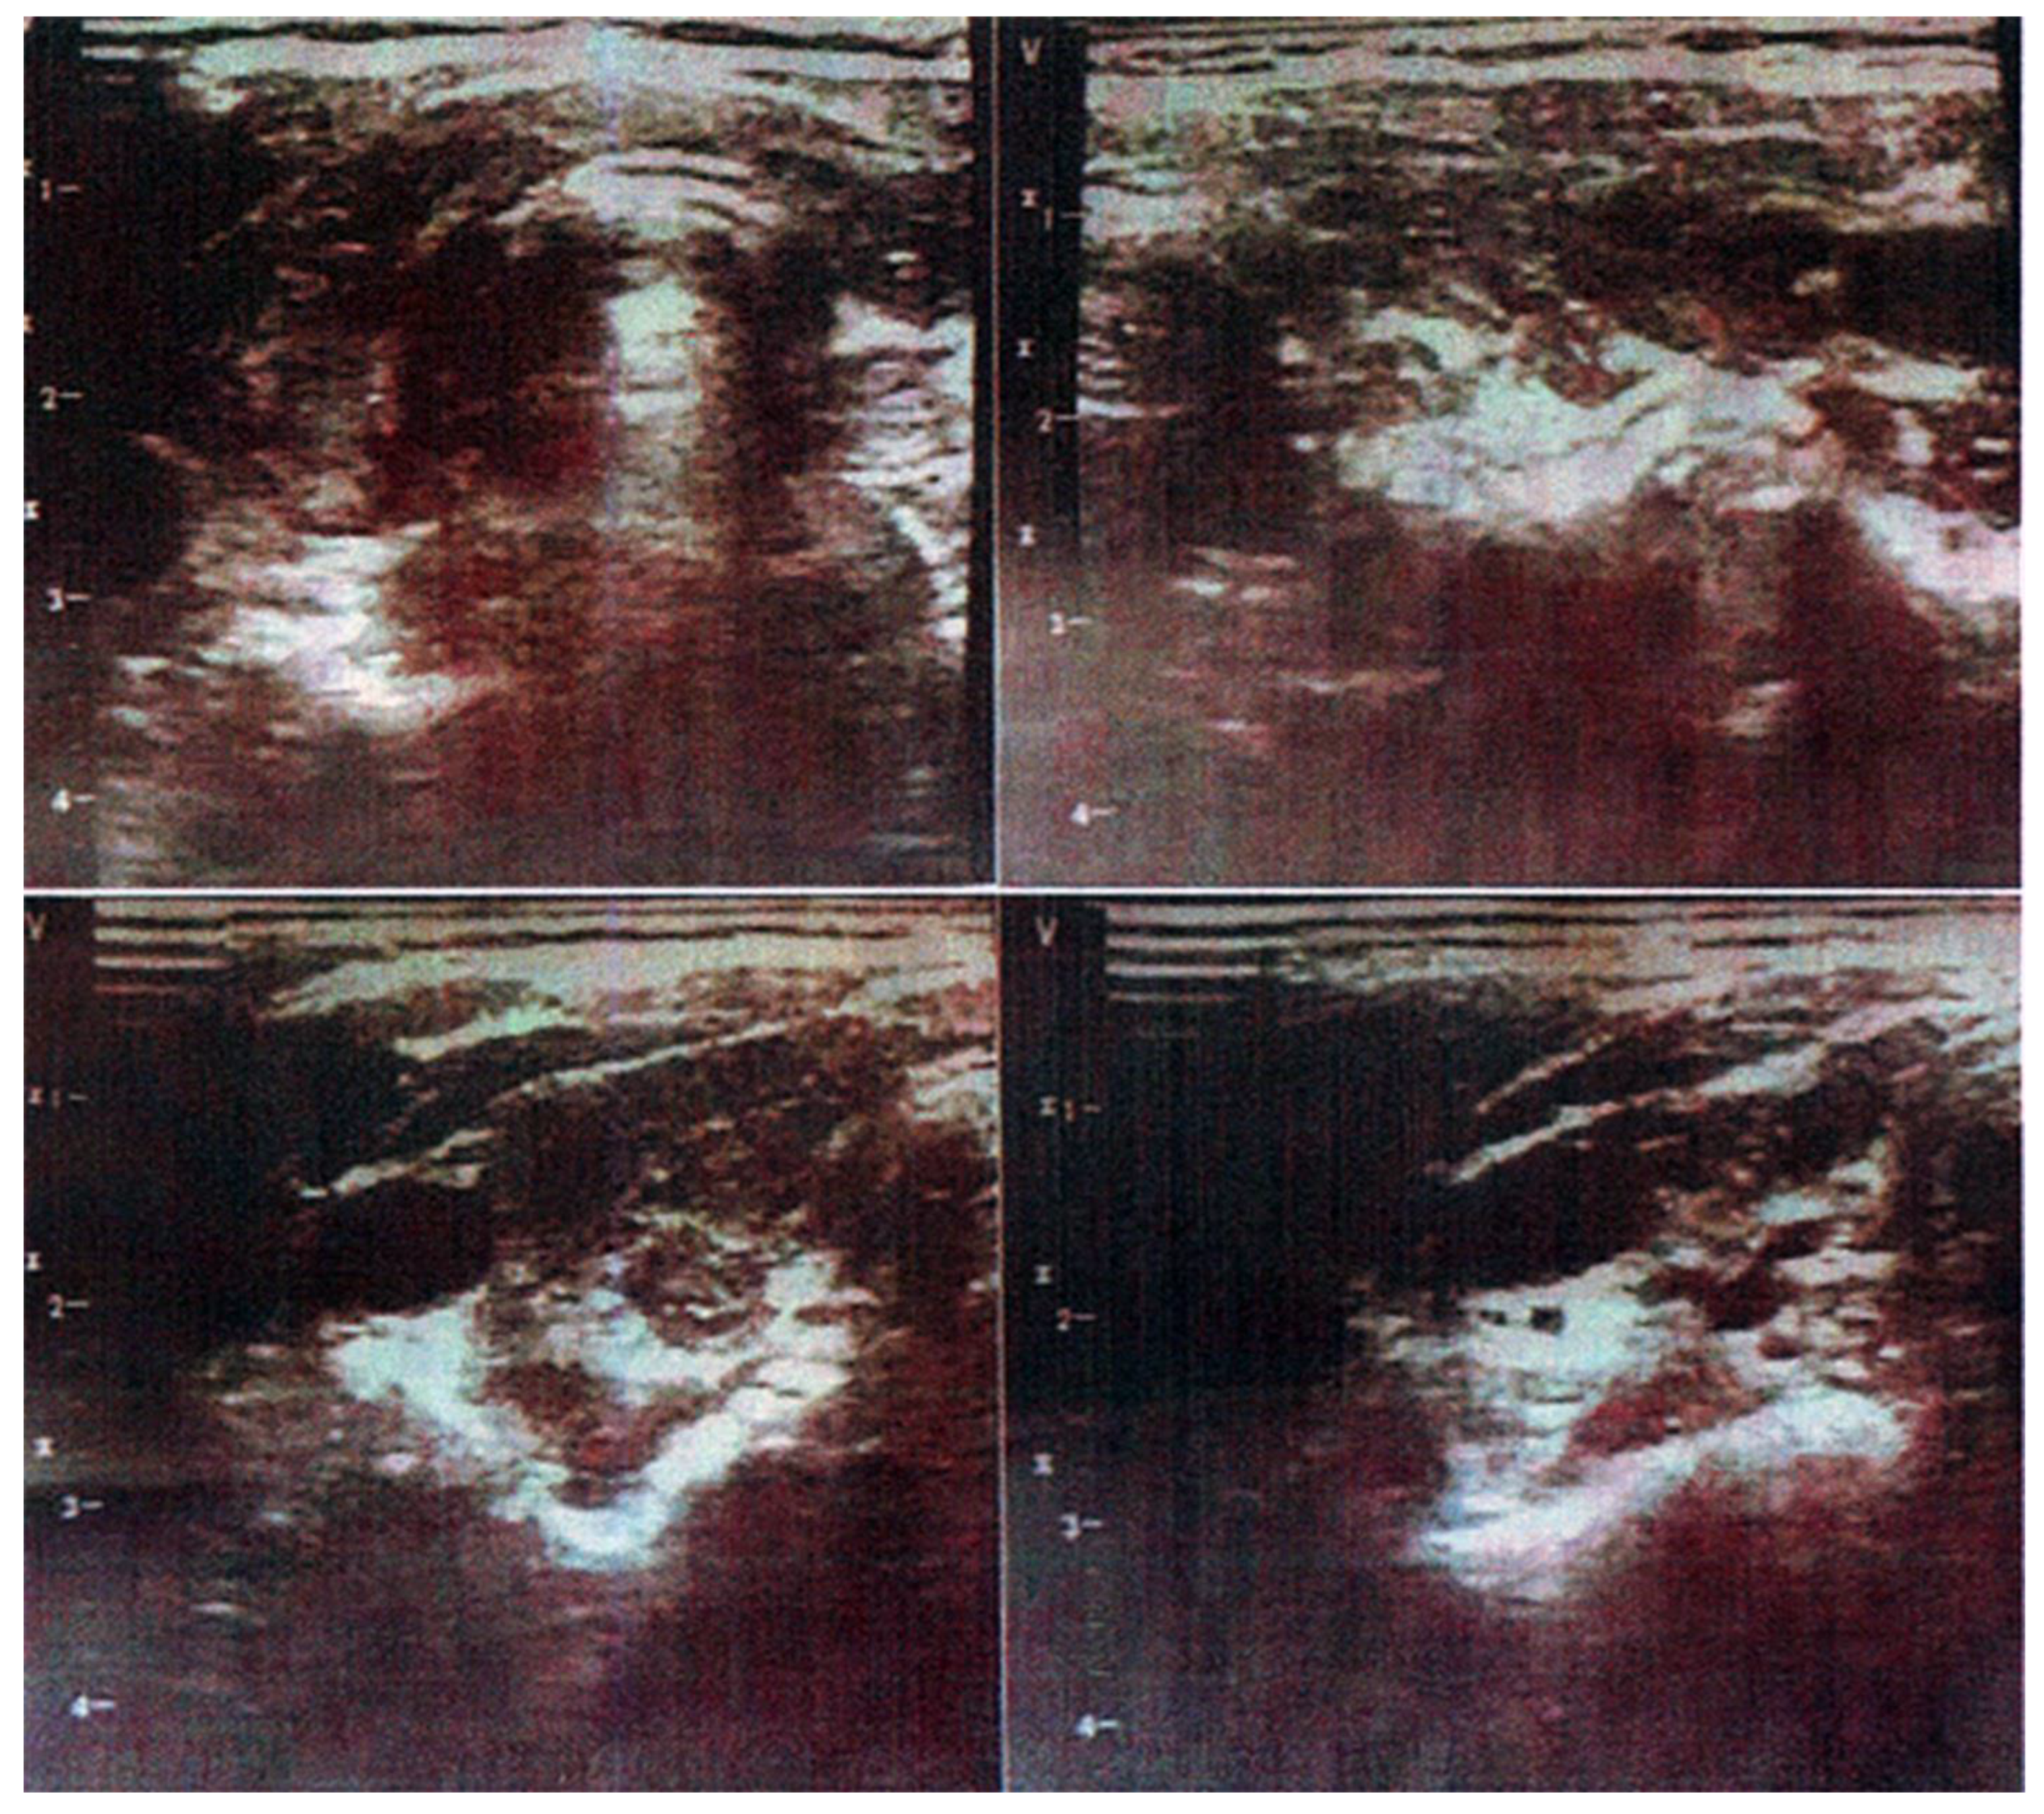

2.1. Case 1

2.2. Case 2